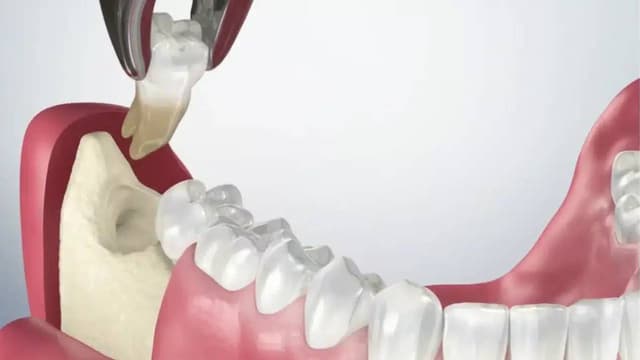

Nhổ răng khôn để lại lỗ: Bí quyết giảm sưng đau hiệu quả

Việc phát hiện một lỗ hổng tại vị trí răng khôn vừa nhổ là điều khiến nhiều người lo lắng. Tuy nhiên, đây là một phần hoàn toàn bình thường của quá trình lành thương. Tình trạng nhổ răng khôn để lại lỗ sẽ sớm được khắc phục nếu bạn hiểu rõ nguyên nhân và […]